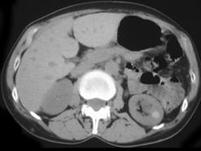

问题 女,38岁,无特殊临床表现,根据影像,选择最有可能的诊断 ( )

选项 A、左肾高密度囊肿 B、左肾单纯性囊肿并感染 C、左肾单纯性囊肿 D、左肾钙化性囊肿 E、左肾癌

答案 A